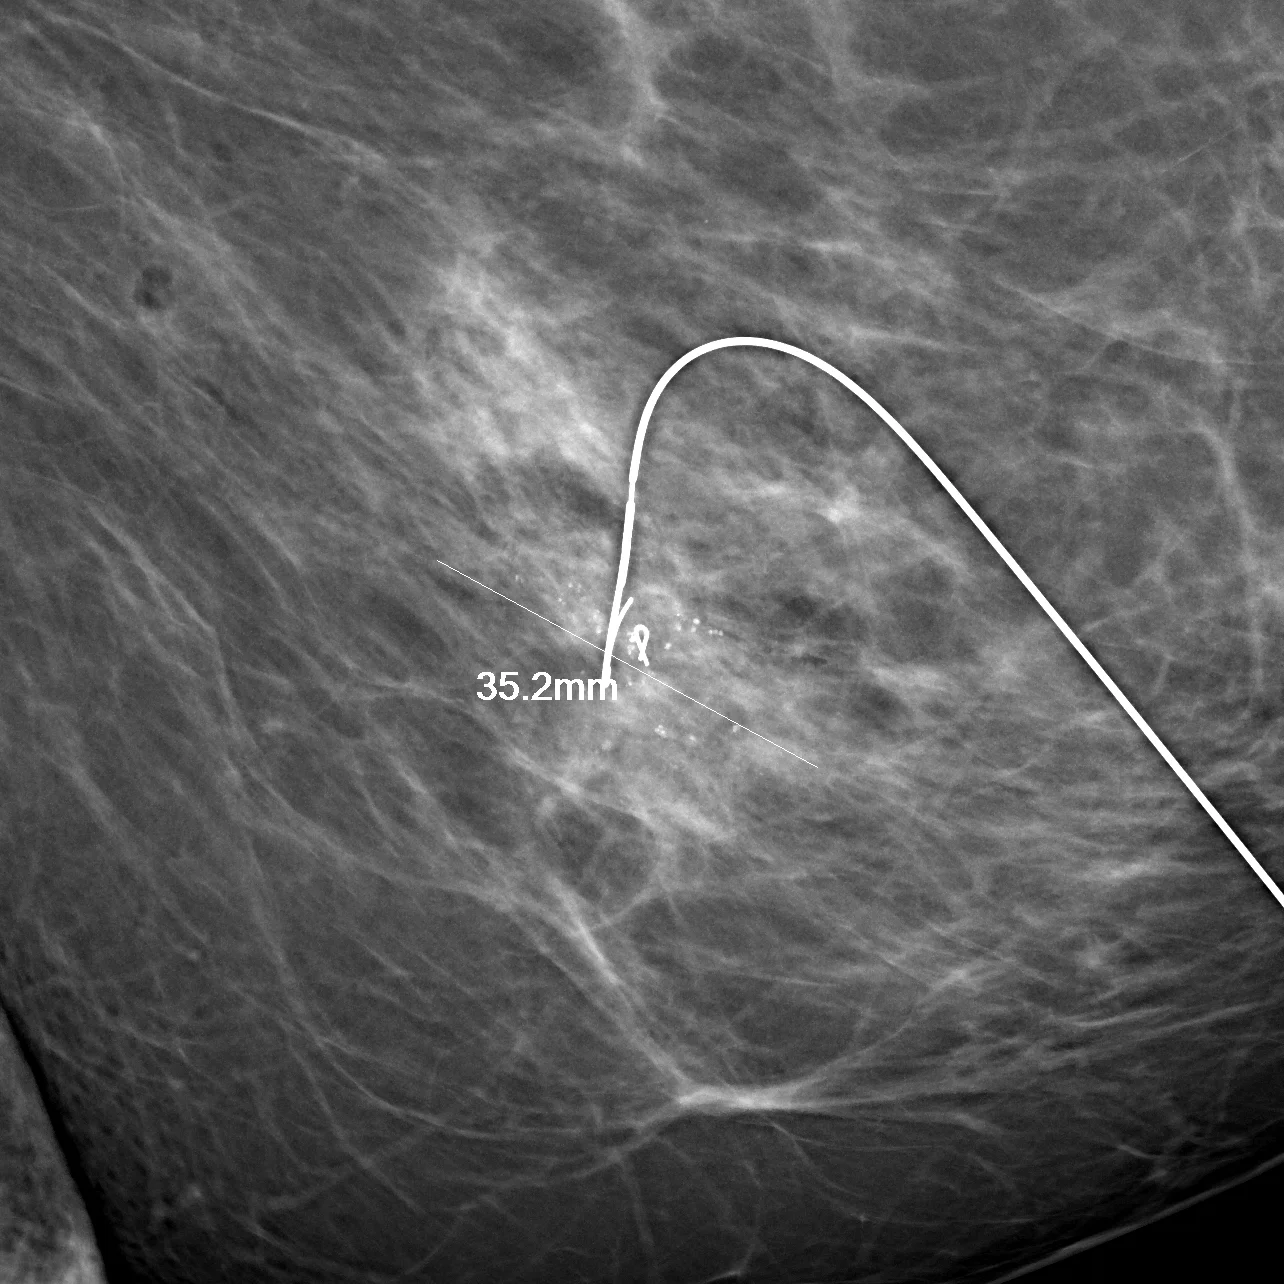

Surgical localization and planning on the Giotto. Direct measurement of the cancer and placement of localization devices with millimetric precision decreases reexcision rates while minimizing the amount of tissue that has to be removed.

Designed not just for imaging, but for imaging guidance, our Giotto mammography system allows for the easy localization and biopsy of any finding that we can see on mammogram. This includes small areas of microcalcifications as well as mass lesions.  Biopsies can be performed in the position of the client's best comfort.